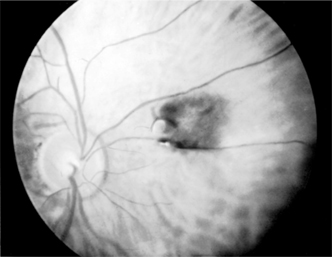

It has been estimated that intraocular malignant melanoma occurs in 0.02-0.06% of the total eye patient population in the USA. It is seen only in the uveal tract and is the most common intraocular malignant tumor in the white population. It is almost always unilateral. Eighty-five percent appear in the choroid (Figure 7-9), 9% in the ciliary body, and 6% in the iris.

Figure 7-9

Figure 7-9: Malignant melanoma of the choroid, macular area, left eye (drawing). (Courtesy of F Cordes.)

This tumor may be seen in its early stages only accidentally during routine ophthalmoscopic examination or because of blurring due to macular invasion. Blood-borne metastases may occur at any time. Glaucoma may be a late manifestation.

Clinical manifestations are usually absent unless the macula is involved. In the later stages, growth of the tumor may lead to retinal detachment with loss of visual field. A tumor located in the iris may change the color of the iris or deform the pupil. Pain does not occur in the absence of glaucoma or inflammation.

The first step in diagnosis is to suspect the lesion. Most intraocular malignant melanomas can be seen ophthalmoscopically. Always suspect the presence of a tumor in eyes with nonrhegmatogenous retinal detachment. A significant incidence of intraocular melanomas has been found in blind, painful eyes; ultrasonography will help detect these.